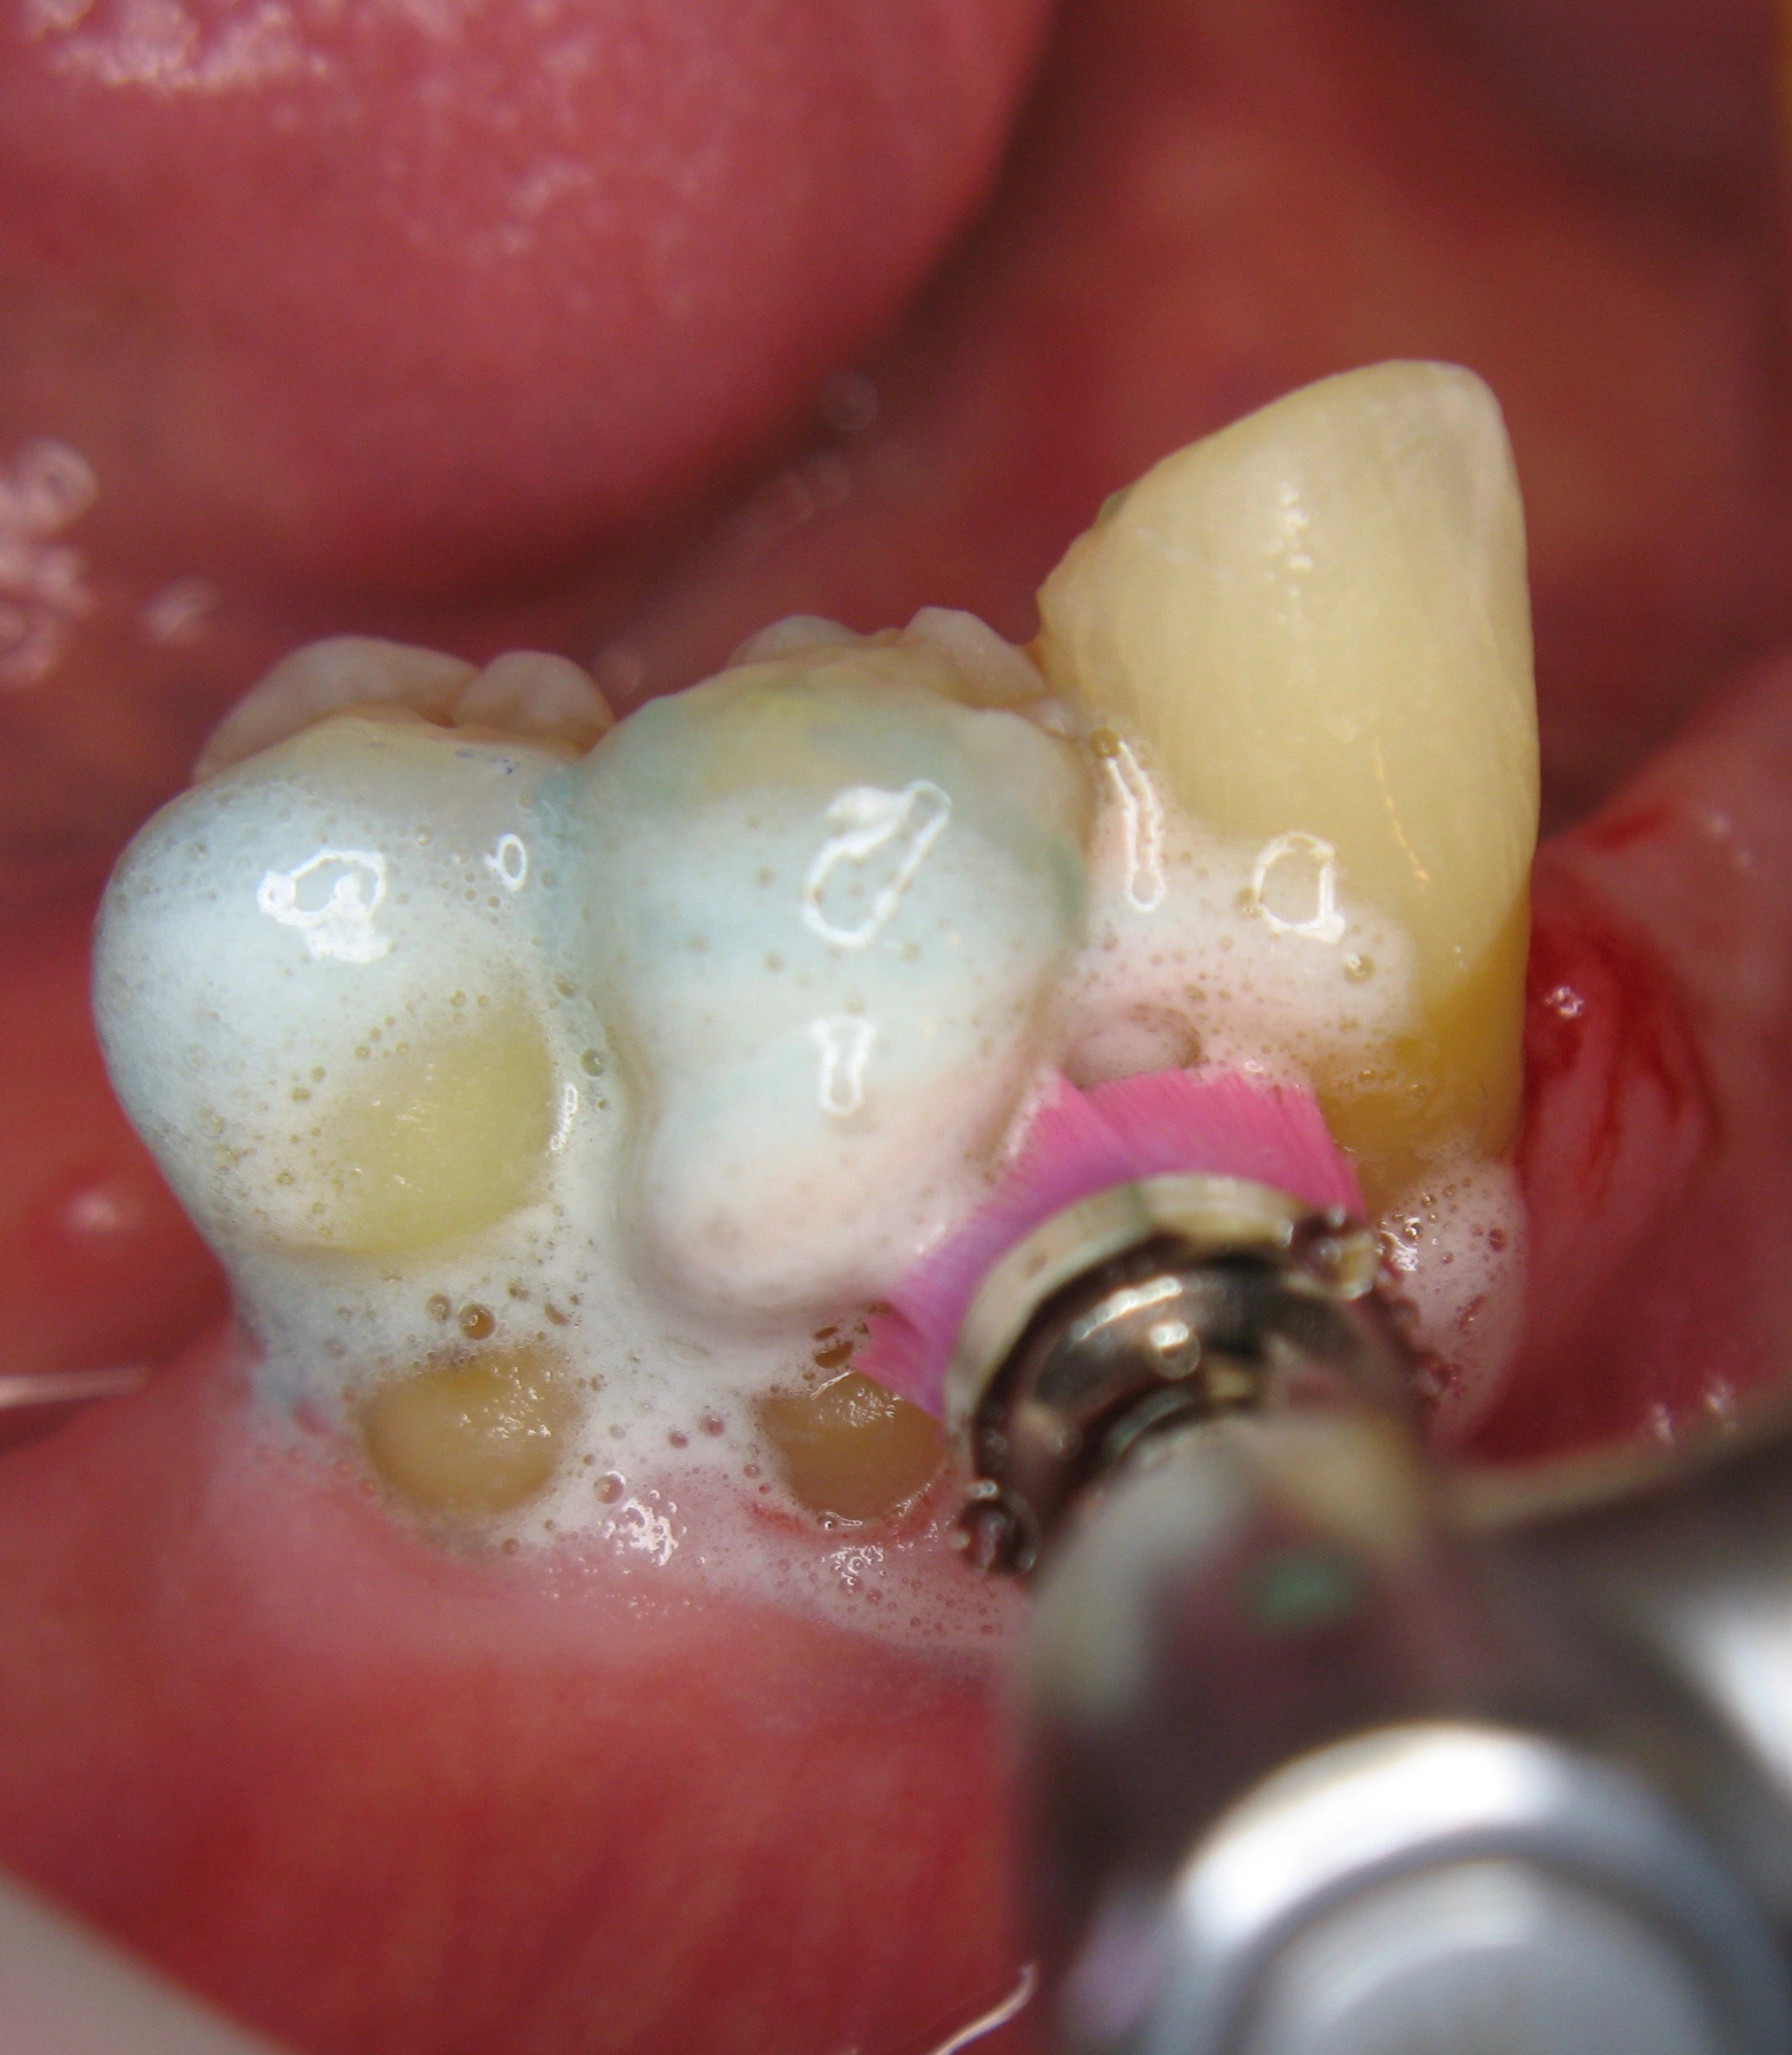

Der Patient (männlich, 72 Jahre alt) war vor der Behandlung bereits seit vielen Jahren parodontal erkrankt. Aufgrund der Einnahme verschiedener Medikamente litt er zudem unter Mundtrockenheit, so dass der Speichel seine wichtige Funktion als schützender Puffer für den Zahnschmelz nur ungenügend erfüllen konnte. Der Patient wies ausgeprägte Zahnhalsdefekte mit Rezessionen auf (Abb. 1 u. 2) und reagierte nach der Parodontalbehandlung schmerzempfindlich auf Heißes, Kaltes oder Süßes. Zudem zeigten sich mehrere kariöse Läsionen.

Unsere Therapie in der Praxis sieht eine dreimal jährliche UPT vor, bei der regelmäßig im Bereich der freiliegenden Zahnhälse mit Duraphat® Fluorid 5mg/g Zahnpaste eingebürstet wird (Abb. 3-5). In unserer Mundhygieneinstruktion empfahlen wir dem Patienten, eine Zahnbürste mit weichem Borstenfeld oder alternativ eine elektrische Zahnbürste mit Drucksensor zu nutzen, um zu stark abrasives Putzen zu verhindern. In der Ernährung sollte der Patient auf möglichst weiche und cremige Kost achten und die Trinkmenge erhöhen, um die Schleimhäute regelmäßig zu befeuchten. Zur Verringerung der Mundtrockenheit eignen sich auch speichelanregende Nahrungsergänzungsmittel oder saure, zuckerfreie Bonbons.